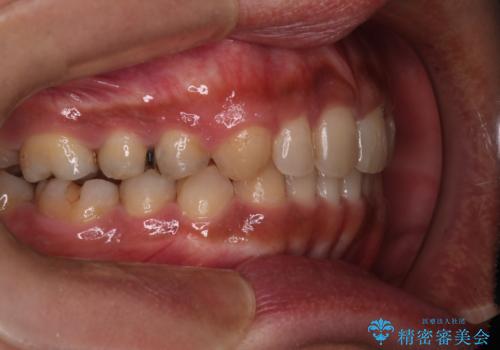

【モニター】インビザライン 前歯の捻れを治したい

- 30代男性

- 矯正装置

- インビザライン

- 治療期間

- 1年6ヶ月

- 上下の前歯のがたつきを主訴に来院されました。インビザラインで治療可能と判断致しましたので、IPR(歯と歯の間を削る処置)と歯列弓拡大をして

がたつきをとる治療計画を立てました。

マウスピースをしっかり使用していただいたことで、主訴である前歯のがたつきも改善され

リファイメントも1回のみで治療を終了することが出来ました。